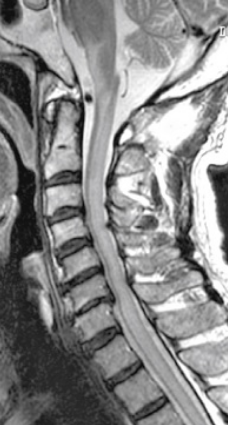

1、再次手术切除:如患者自身条件符合再次手术切除的标准,一般手术可以处理复发的肿瘤。针对脊髓肿瘤的手术切除,显微外科手术是主要的方法,近年来显微外科器械、手术技术的进步,成功率提高,致残率下降。再次手术难度和风险均是增大了很多,选择手术的医生要谨慎,否则不仅不能切干净,而且术中还可能导致危险。目前,INC国际神经外科医生集团旗下国际神经外科顾问团成员巴特朗菲教授、Sebastien Froelich教授、James T. Rutka教授作为国际脑瘤手术教授,他们不仅能对脊髓肿瘤实施高切除率手术,而且术后神经功能无明显损伤,让患者的生活质量也较术前有了很大的提高。

2、放射治疗。对于无法再次手术切除、或者手术仍然有残余肿瘤的脊髓肿瘤患者,放疗是临床常用的策略。脊髓肿瘤有些位置手术注定难以切除干净,放疗可用于消除手术后残留的肿瘤残余。不能手术的肿瘤或手术风险太大的肿瘤,这时候可以通过放射治疗加以辅助,来帮助控制、减少受损细胞,让治疗效果更好。